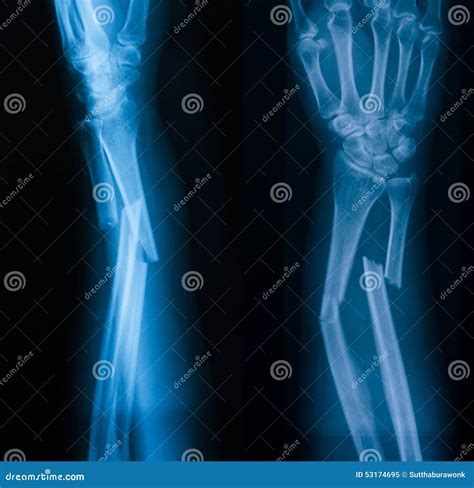

To interpret a forearm X-ray, it helps to understand the anatomy involved. The forearm consists of two long bones that work together to allow for flexibility and rotation:

The Radius: Located on the side of the thumb, the radius is the bone that primarily allows the forearm to rotate, enabling you to turn your palm up or down.

The Ulna: Located on the side of the pinky finger, the ulna is larger at the elbow and helps form the hinge joint necessary for bending the arm.

Injuries to these bones often occur during a "FOOSH"—an acronym for Fall On an Outstretched Hand. When you fall, the impact travels up through the wrist and can easily fracture either or both of these bones. Because they are anatomically linked, a fracture in one often causes structural stress or a corresponding dislocation in the other.

• Fractures: Whether the bone is broken completely, partially (a hairline fracture), or fragmented (comminuted fracture).

• Alignment: Checking if the broken ends of the bone are touching or if they have shifted.